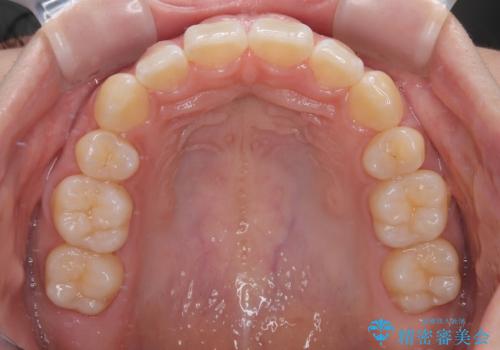

- ハーフリンガル

上下前歯が嘴のように前方に突出しており、唇が閉じにくい状態であったため、上下左右の第一小臼歯4本を抜歯して、口元の突出感を改善することとしました。

口元の印象が劇的に解消され、気にしていたガミースマイルも図らずも改善することができました。